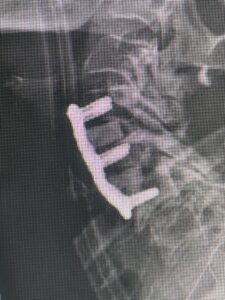

(Fig 1) Hydroxyapatite Coated Pedicle Screw

Pedicle screws can be coated with a thin layer of hydroxyapatite (Fig. 1), which is a natural form of calcium apatite present in human bone and plays a role in the structural strength of bone and in bone regeneration. By coating the screws with hydroxyapatite this can improve screw fixation or bonding at the bone-implant interface